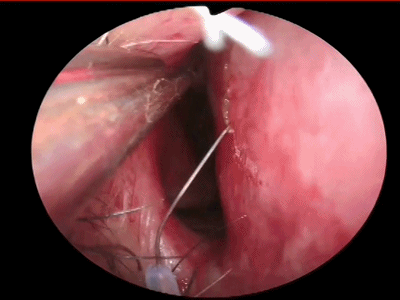

▼用鼻中隔剥离子分离切口侧鼻中隔软骨膜及骨膜,弯曲面向软骨及筛骨垂直板分离时自上而下并与鼻梁平行分离黏软骨膜直至犁骨,此部位软骨膜常有粘连愈着,分离时应用宽钝器械,不要用小而锐的器械,以避免穿孔。

![]()